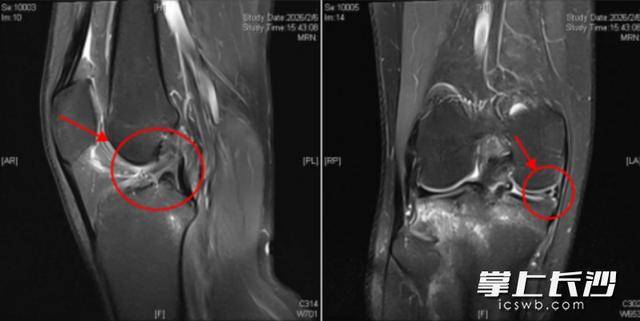

3月1日,他來到長沙市中心醫院運動醫學科主任醫師餘敏的門診,經詳細查體並結合磁共振檢查,確診其為前交叉韌帶斷裂合併半月板撕裂留學。為了恢復關節的穩定以及防止繼發軟骨損傷,餘敏為其實施關節鏡下前交叉韌帶重建+半月板縫合修復術,術後患者恢復順利,目前在進行後續的康復訓練。

餘敏介紹,前交叉韌帶斷裂合併半月板損傷,是運動中較為常見的膝關節複合損傷,二者常常 “相伴而來”留學。前交叉韌帶位於膝關節內,連線股骨與脛骨,是維持膝關節穩定性的核心結構,如同膝關節的“穩定帶”,能有效限制脛骨向前過度移位,讓人體順利完成跳躍、急停、變向等複雜的下肢動作。而半月板則是膝關節內的“緩衝墊”,起到減震、分散壓力、輔助關節穩定的作用。在足球、籃球等對抗性較強的運動中,膝關節突然的扭轉、外翻,極易同時造成前交叉韌帶的撕裂與半月板的損傷。

對於前交叉韌帶斷裂合併半月板損傷,針對這類膝關節複合損傷,早期微創手術是目前的最佳治療方案留學。膝關節受傷後,應第一時間停止運動,前往專業的運動醫學科室就診,透過醫生查體、磁共振(MRI)檢查,精準判斷損傷的部位與程度。關節鏡微創手術具有創傷小、恢復快、康復效果好的特點,能在精準修復斷裂的前交叉韌帶同時,處理受損的半月板,最大程度保留膝關節的正常功能,降低術後併發症風險,幫助運動愛好者儘可能重返賽場。